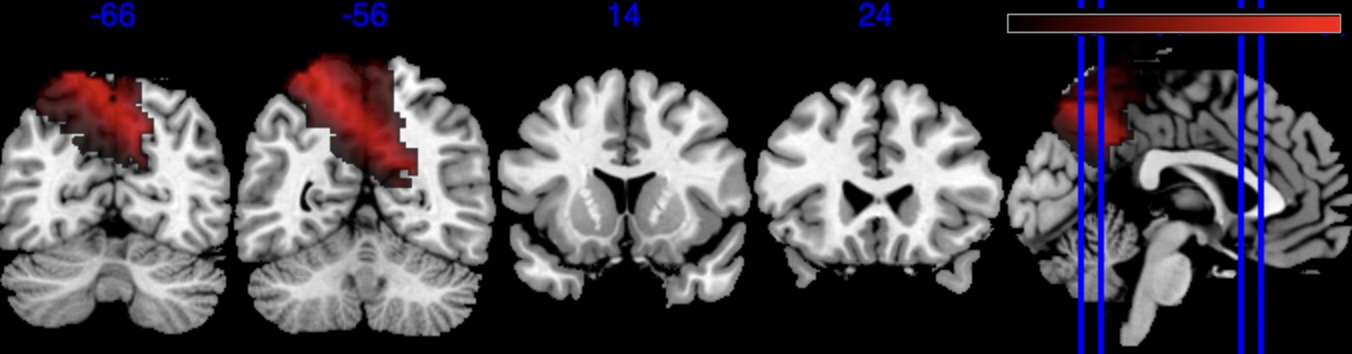

We performed 100,000 iterations for the outcome model (1), discarding the first 50% as burn-in and thinning to retain 1,000 posterior samples. For the mediator model (2), we ran 40,000 iterations with a 30,000 burn-in, thinning every 10 iterations to obtain 1,000 posterior samples. Table 3 gives a summary of both the overall NIE and NDE and the top seven regions identified with the largest number of active voxels. The definition of NIE in each region is , where is the collection of all voxels in region . The rule for selecting the active voxels is based on cutting the posterior inclusion probability (PIP) at 50%, and the three regions with active voxels are reported in Table 3. Due to the very small effect sizes and low signal-to-noise ratio, we also include regions with voxels’ PIP greater than 10%. The posterior of NDE has a mean of 0.27 with the 95% credible interval . The posterior of NIE has a mean of 0.0885 with the 95% credible interval . The total effect of parental education level on general cognitive ability score is 0.36, with 95% credible interval (0.29,0.45). This suggests that parents with college degrees have a positive impact on children’s cognitive abilities, and about 25% of the effect is mediated through brain cognitive development. Figure 5 shows the estimated activation regions and the NIE in coronal view slides. Among the top identified activation regions, the most interesting is the left precuneus, which plays a key role in episodic memory, visuospatial processing, and self-consciousness (lou2004parietal; wallentin2006parallel). This region has been consistently implicated in cognitive processes related to memory retrieval and spatial awareness, which are crucial components of children’s cognitive development. In addition, other identified regions, such as the left inferior parietal region and the left postcentral gyrus, are associated with the interpretation of sensory information (radua2010neural; diguiseppi2023neuroanatomy). These regions are involved in integrating and processing sensory inputs, which are essential for tasks that require coordination between perception and cognition, such as working memory and executive function. These findings align with existing literature on the neural correlates of cognitive function, particularly in children. By identifying regions that have been consistently associated with cognitive processes, our results not only demonstrate the scientific validity of the BIMA approach but also provide meaningful insights into the brain areas that underlie cognitive abilities as captured by the ABCD study.

| Posterior inclusion probability (color range ) |

![]() |

| Positive posterior mean of the spatial mediation effects (color range ) |

| Negative posterior mean of the spatial mediation effects (color range ) |